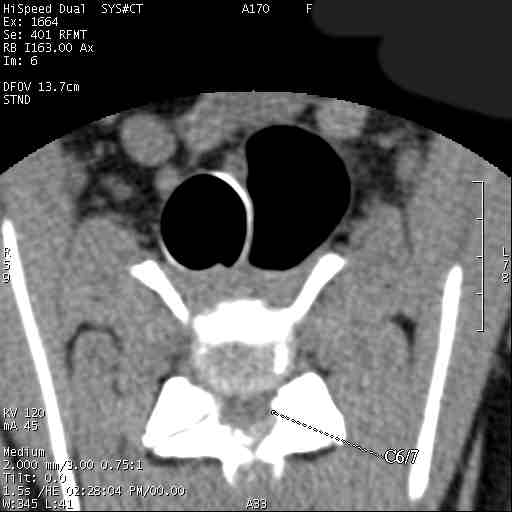

Im folgenden Beispiel sieht man computertomografische Bilder der Halswirbelsäule einer Dogge mit folgender Diagnose: Knöcherne Stensoe C3/4 [= 3./4. Halswirbel], sanduhrförmige Kompression des Myelons auf der Höhe C3/4, Bandscheibenvofall C6/7 [= 6./7. Halswirbel], Myelon mit seitlicher Abweichung nach links : Im Ergebnis eine Halswirbelstenose an den beiden Stellen mit Kompression des Myelons, die zu den Lähmungserscheinungen führt.